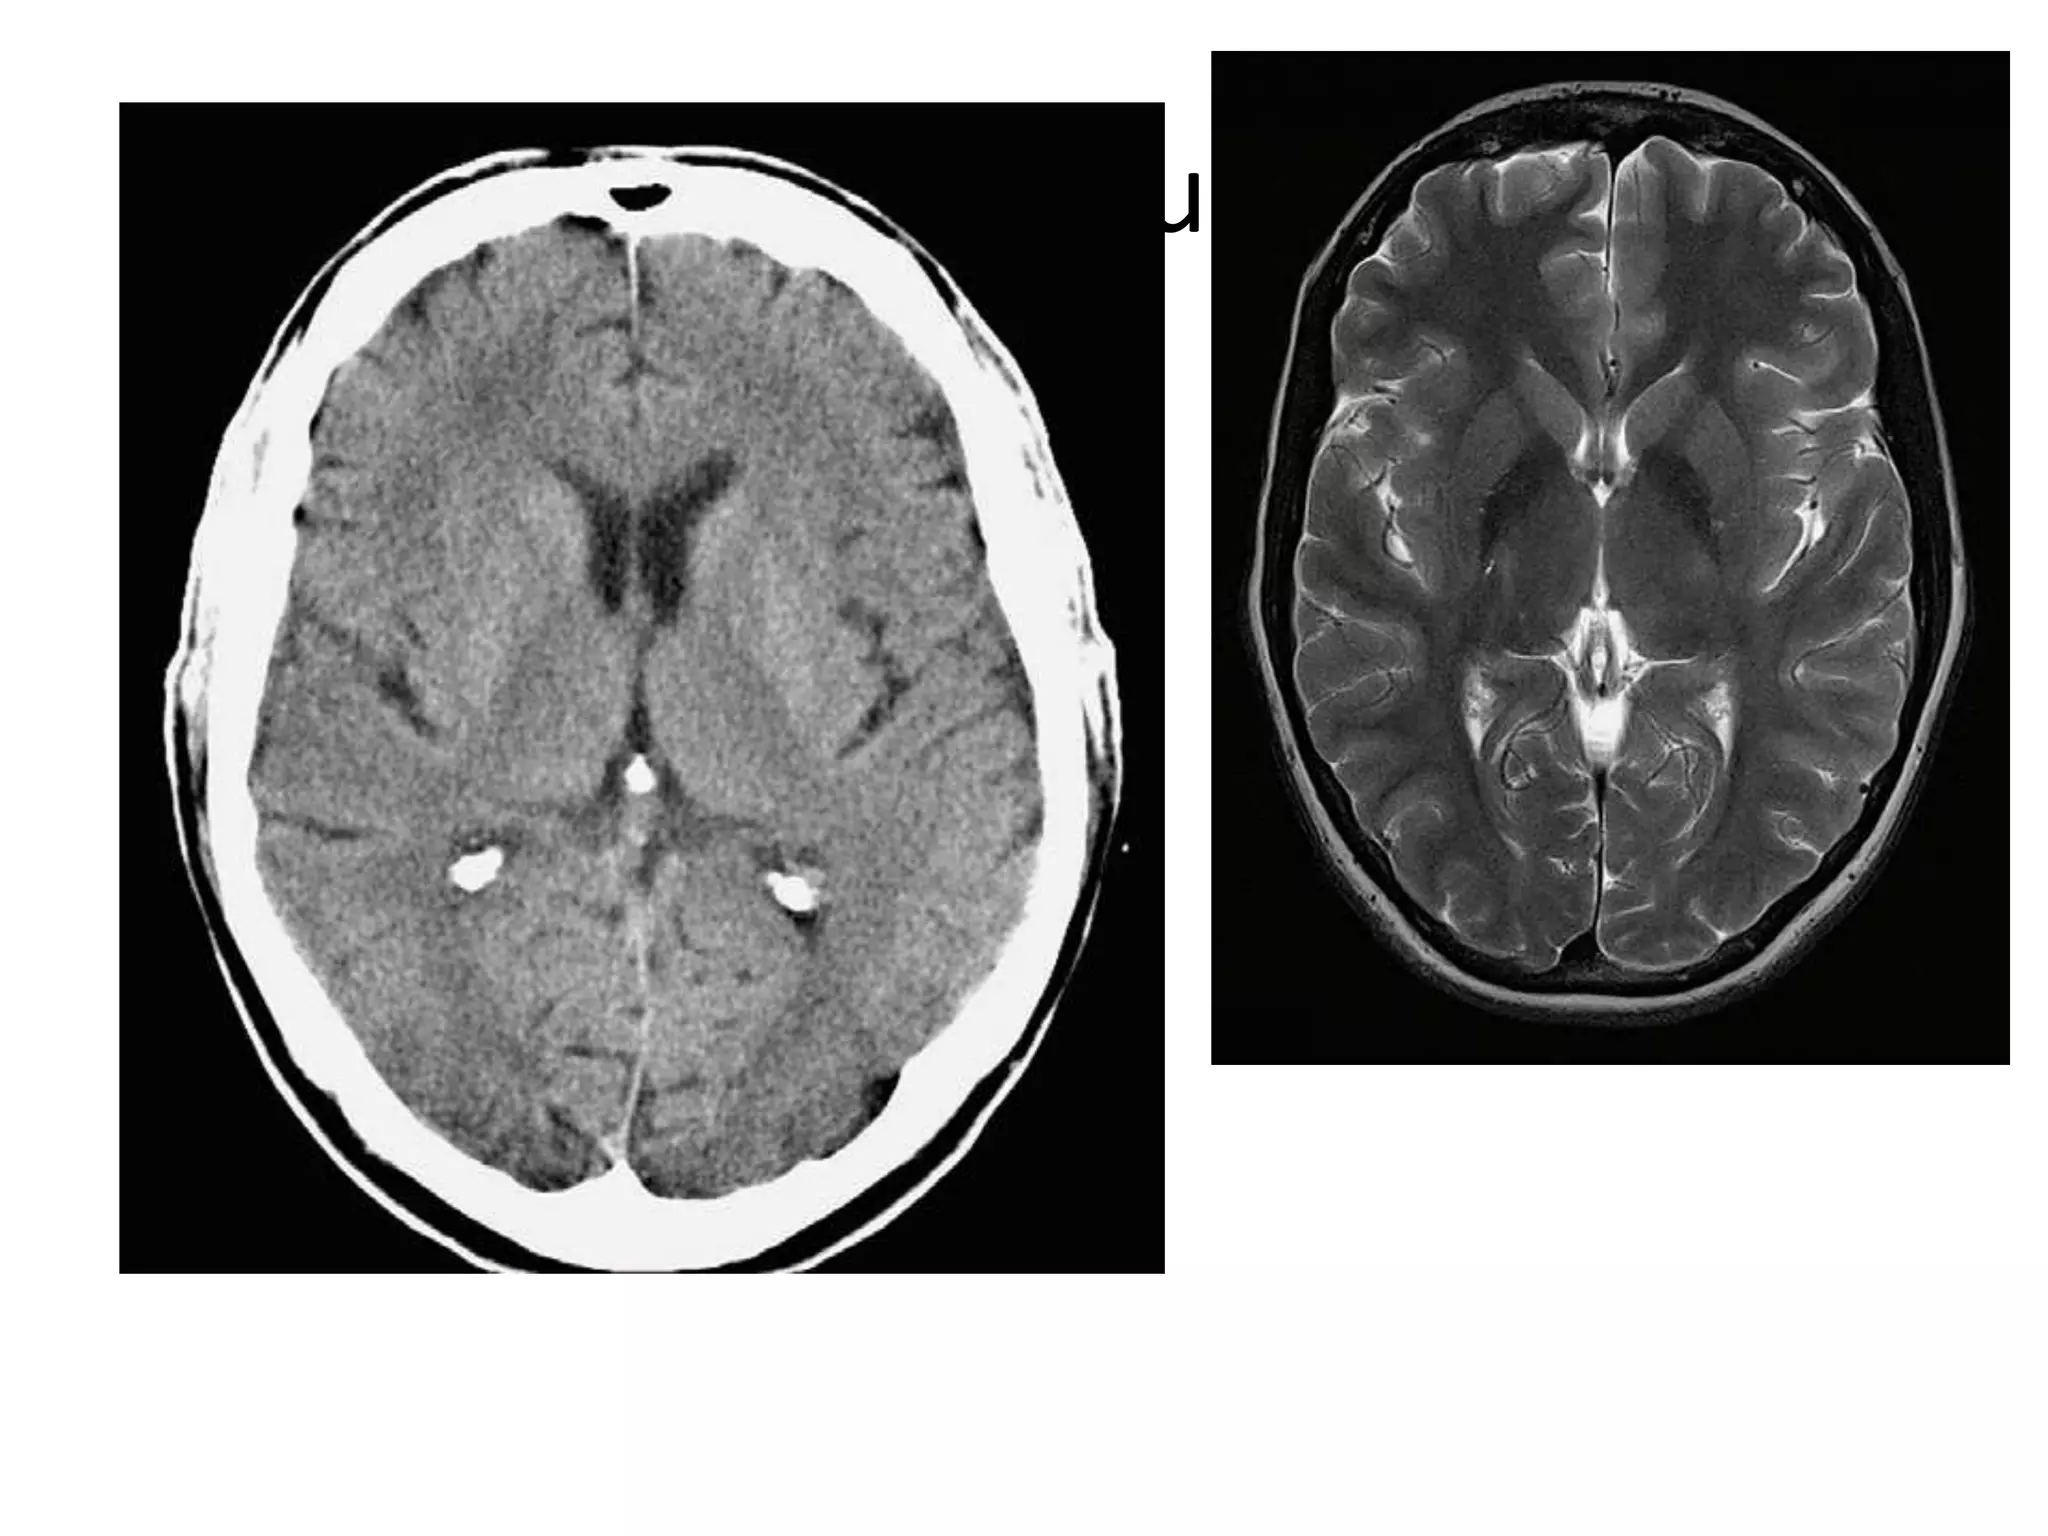

• On axial CT , structures medial to line of tentorial

edge are infratentorial and those lateral are

supratentorial.

Axial MRI / CT : frontal horns separated by

S. pellucidum and posteriorly lateral ventricles diverge

and pass into temporal and occipital horns.

• Axial MRI / CT – ‘kidney bean’ turned on its side.

• Saggital MRI - mid point of line drawn b/w T. sella

and trocula should intersect middle of 4th

ventricle.